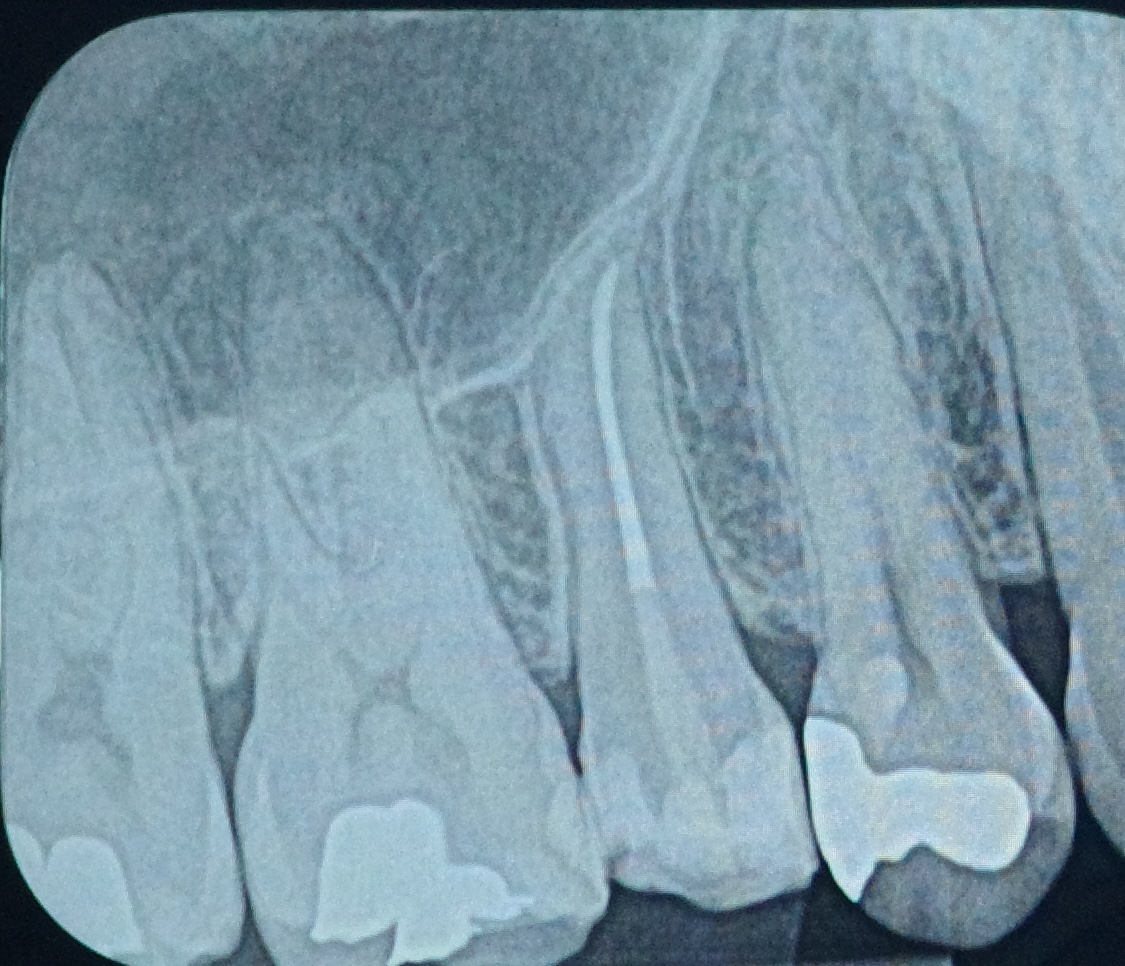

① 根管治療とは?

根管治療は、歯の神経や血管が細菌に感染した場合に行う治療です。感染した神経を取り除き、歯の根の中を清掃・消毒して薬を詰めることで、歯を抜かずに残すことを目的としています。

• デメリット

• 治療回数が複数回に及ぶことがある

• 成功率は症例によって異なり、再治療が必要になる場合がある

• 神経を失った歯は脆くなりやすく、被せ物で補強が必要

• ラバーダム防湿を用いて無菌的に治療

• マイクロスコープやルーペで拡大視野下で精密治療

• 難症例は根管治療専門医と連携

これにより、根管治療の成功率を高め、歯を残す可能性を最大限に引き出します。